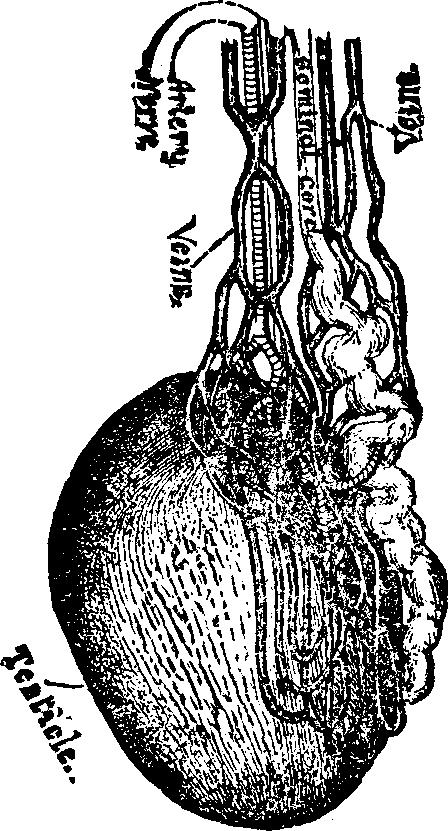

The function of the ovaries is to furnish ova or germs, and the functions of the uterus or womb are to secrete mucus; to exude the menses; to secrete the decidua; to contain and nourish the foetus and to effect its expulsion.